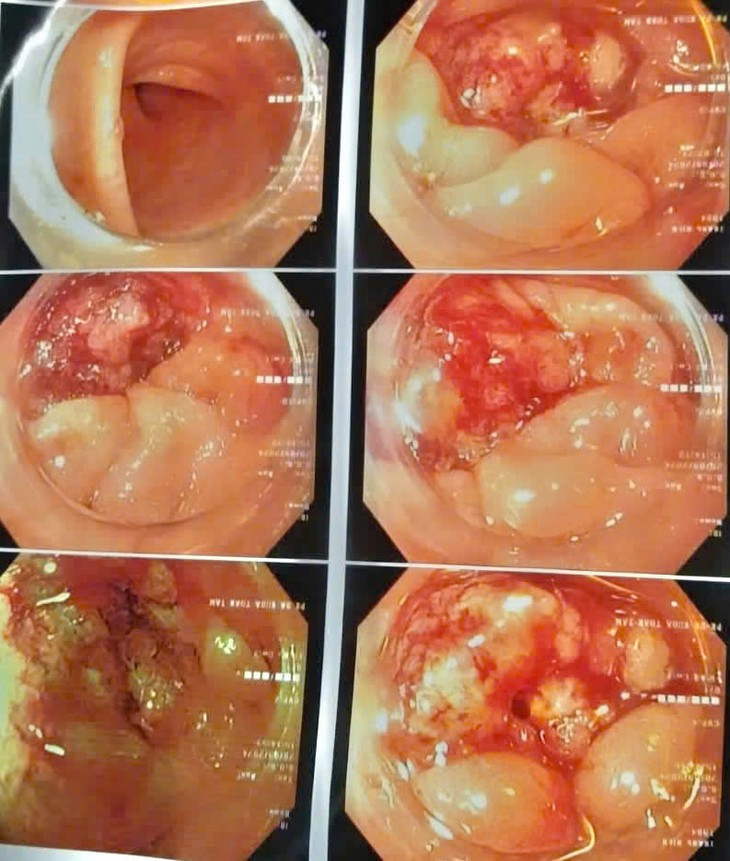

| Hình ảnh tổn thương sùi loét đại tràng qua nội soi. Ảnh BVCC |

Kết quả chụp CT-Scanner ổ bụng và nội soi đại trực tràng cho thấy: xuất hiện nhiều hạch mạc treo đại tràng trái và tổn thương sùi loét đại tràng trái chiếm gần hết chu vi lòng trực tràng.